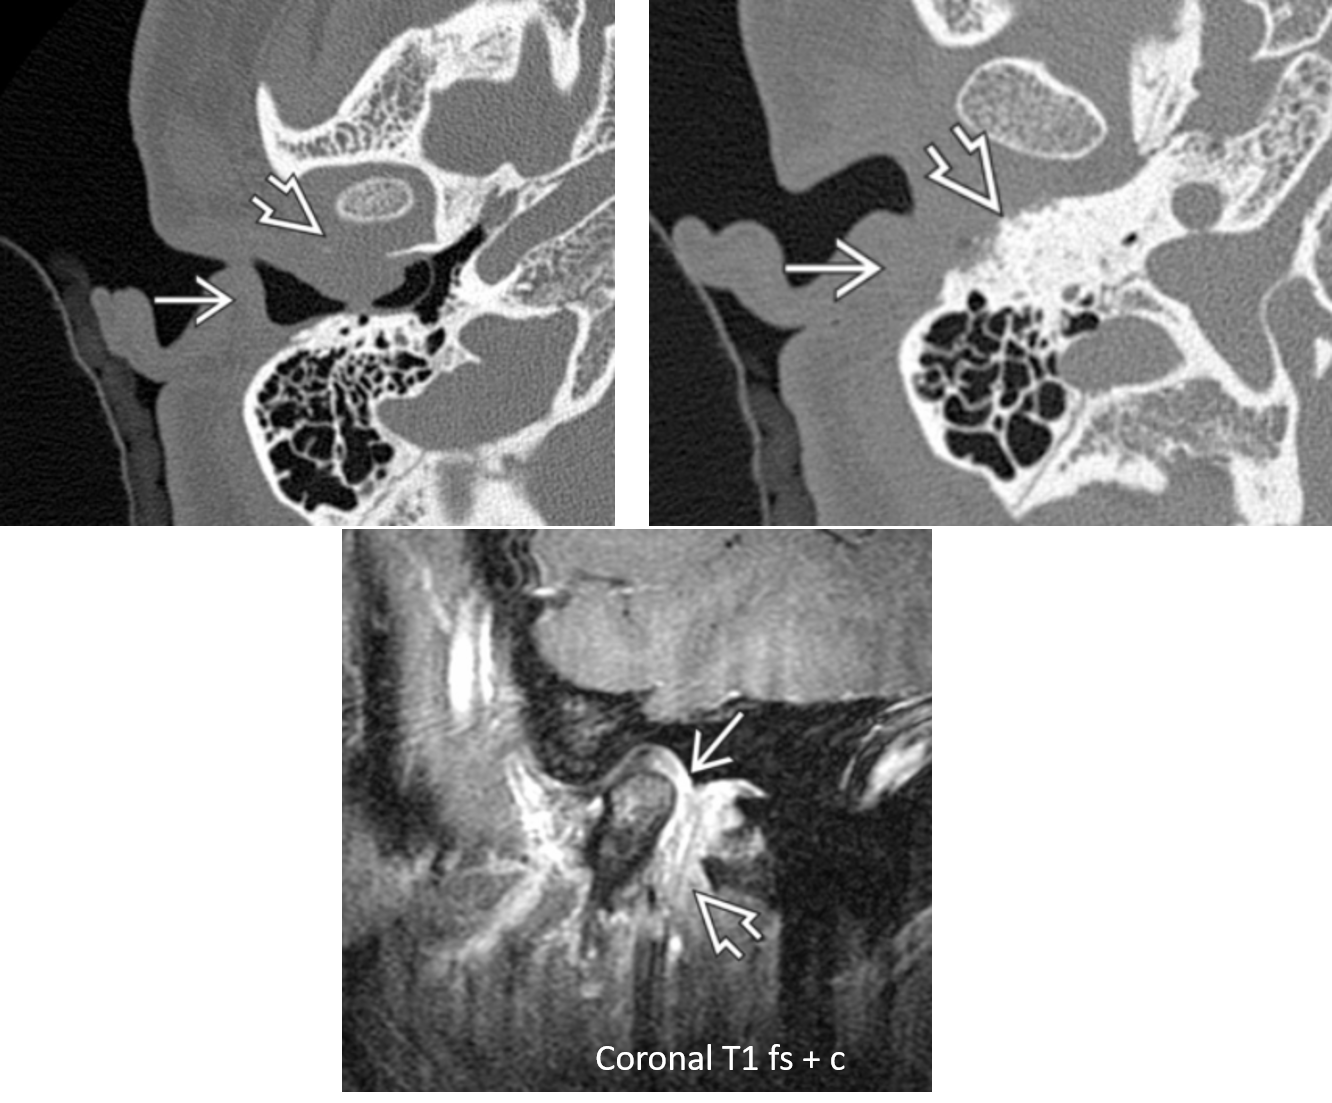

SCC of the EAC on CT and MR

axial bone algorithm CT shows soft tissue density in the EAC with osseous erosion. MR demostrates soft tissue enhancement.

Bone destruction and soft tissue invasion = aggressive malignancy